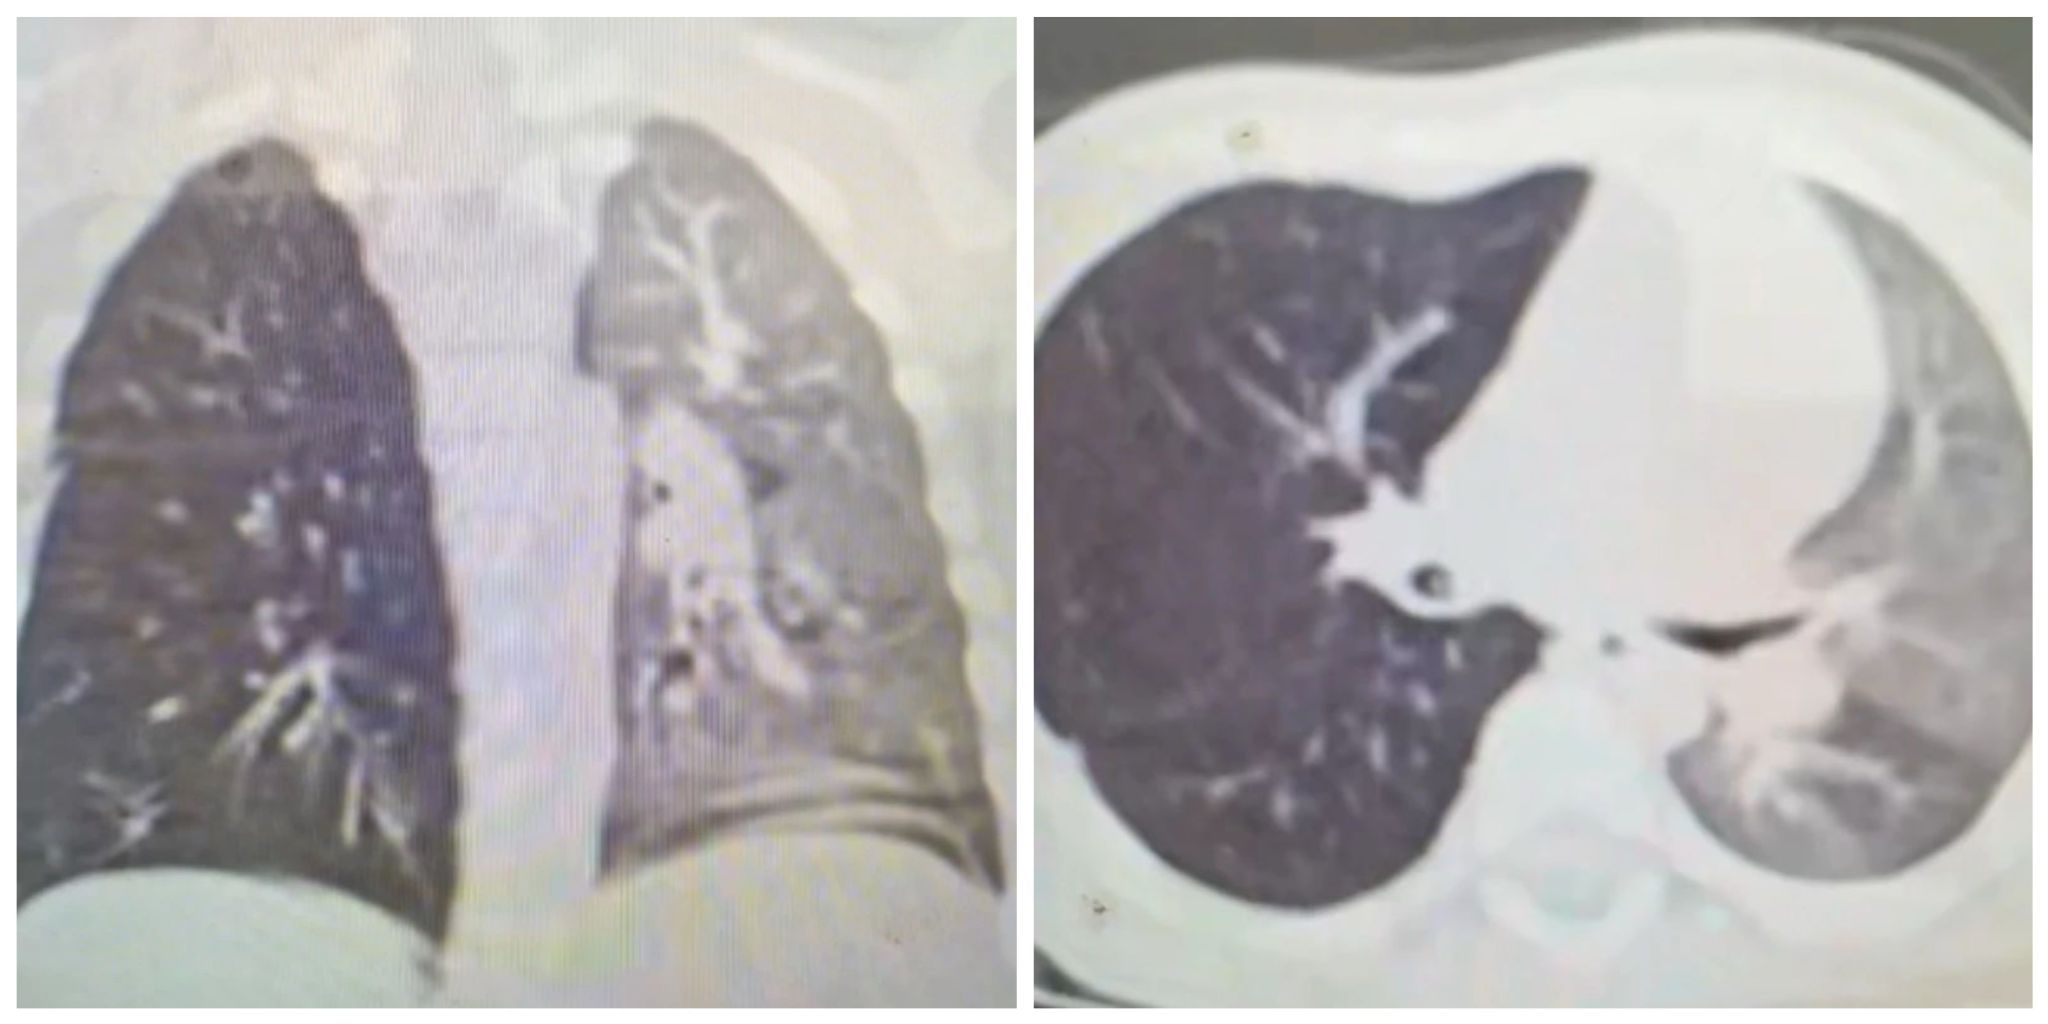

CT影像示患儿右主支气管异物

本网讯(文/孙萌萌 图/董佳乐)1岁宝宝咳喘月余,竟是半颗花生"作祟"。6月18日下午,一名来自平顶山的1岁男童因"反复咳喘1月余"转入麦田影院 儿科二区。此前,孩子在当地医院接受抗感染、雾化治疗后仍无改善,父母心急如焚。接诊医师张贵春发现患儿双肺呼吸音不对称,右肺呼吸明显变低,结合肺部CT影像,凭借临床经验高度怀疑支气管异物。科室气管镜团队立即启动急救流程,连夜加班争分夺秒为患儿行急诊手术。